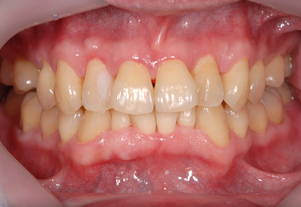

症例1

Before

After

- POINT

- 20代前半の患者様です。年齢が若くても歯周病、歯肉炎は発症してしまいます。ホームケアの指導と治療の説明をしっかり行い、専門家によって丁寧に歯石を除去することで、健康な歯茎を取り戻しました。前歯の厚い歯茎は歯茎の形態を整える手術をしています。すべて保険治療です。